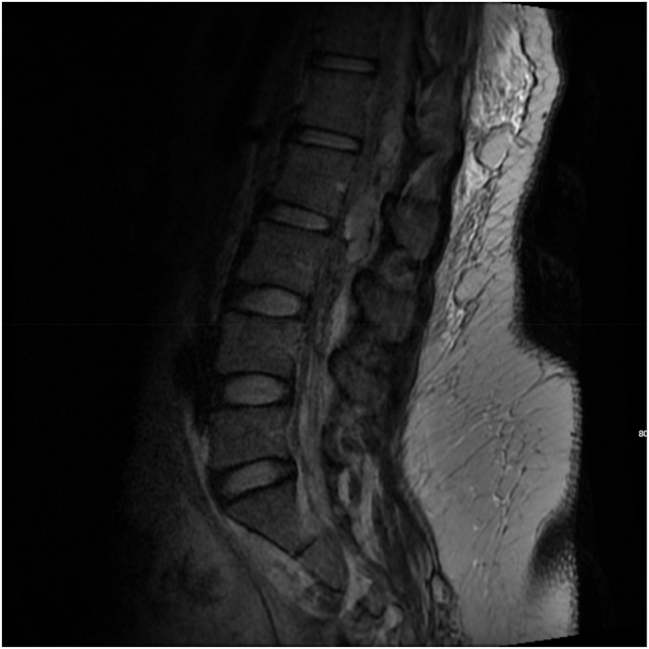

Case presentation: A 31-year-old woman was diagnosed with acquired factor VIII deficiency while undergoing induction of labor. Her labor and post operative course were complicated by epidural hematoma formation, prolonged postoperative surgical site bleeding, and subcutaneous hematoma. Management included blood products, human Factor VII, rituximab, and a steroid taper.